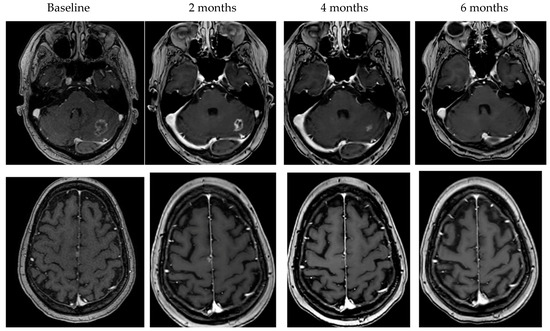

- Bartsch, R.; Berghoff, A.S.; Furtner, J.; Marhold, M.; Bergen, E.S.; Roider-Schur, S.; Starzer, A.M.; Forstner, H.; Rottenmanner, B.; Dieckmann, K.; et al. Trastuzumab deruxtecan in HER2-positive breast cancer with brain metastases: A single-arm, phase 2 trial. Nat. Med. 2022, 28, 1840–1847. [Google Scholar] [CrossRef] [PubMed]

- Pérez-García, J.M.; Batista, M.V.; Cortez, P.; Ruiz-Borrego, M.; Cejalvo, J.M.; de la Haba-Rodriguez, J.; Garrigós, L.; Racca, F.; Servitja, S.; Blanch, S.; et al. Trastuzumab deruxtecan in patients with central nervous system involvement from HER2-positive breast cancer: The DEBBRAH trial. Neuro-Oncology 2022. [Google Scholar] [CrossRef] [PubMed]